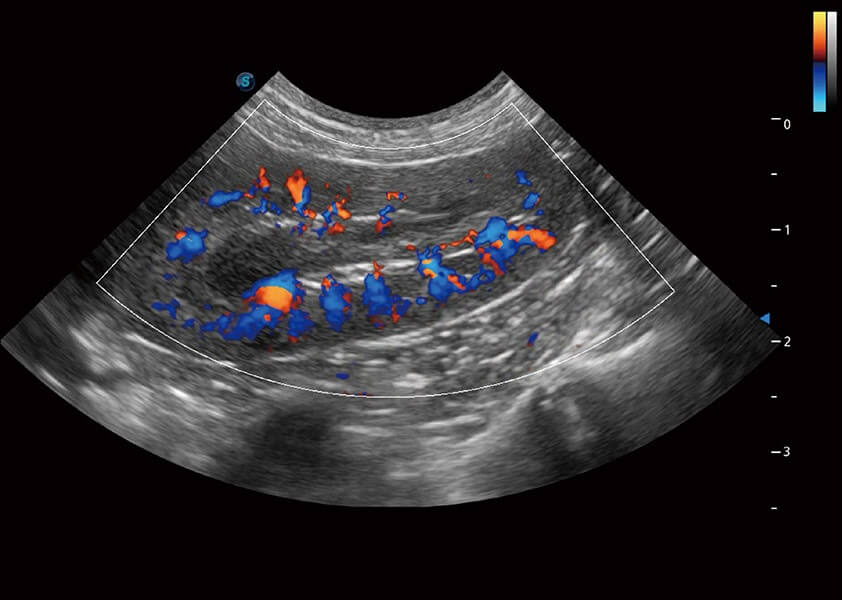

(犬)肾脏血流

4T血流成像 微察秋毫

融合不同血流成像技术的优势,即可以提升血流成束性,同时可提高血流的视觉敏感性。

SR Flow 高分辨率血流成像

能够清晰显示细小、低速血流图像,获取传统彩色多普勒技术难以得到的细节和信息。

Micro F 显微血流成像

通过创新的Matrix E自适应滤波器和超长时间域算法,极大提升超低速微细血流的检出能力,同时更精准地滤除软组织和噪声信号,为兽用医生提供以往无法通过常规血流获得的疾病诊断信息。